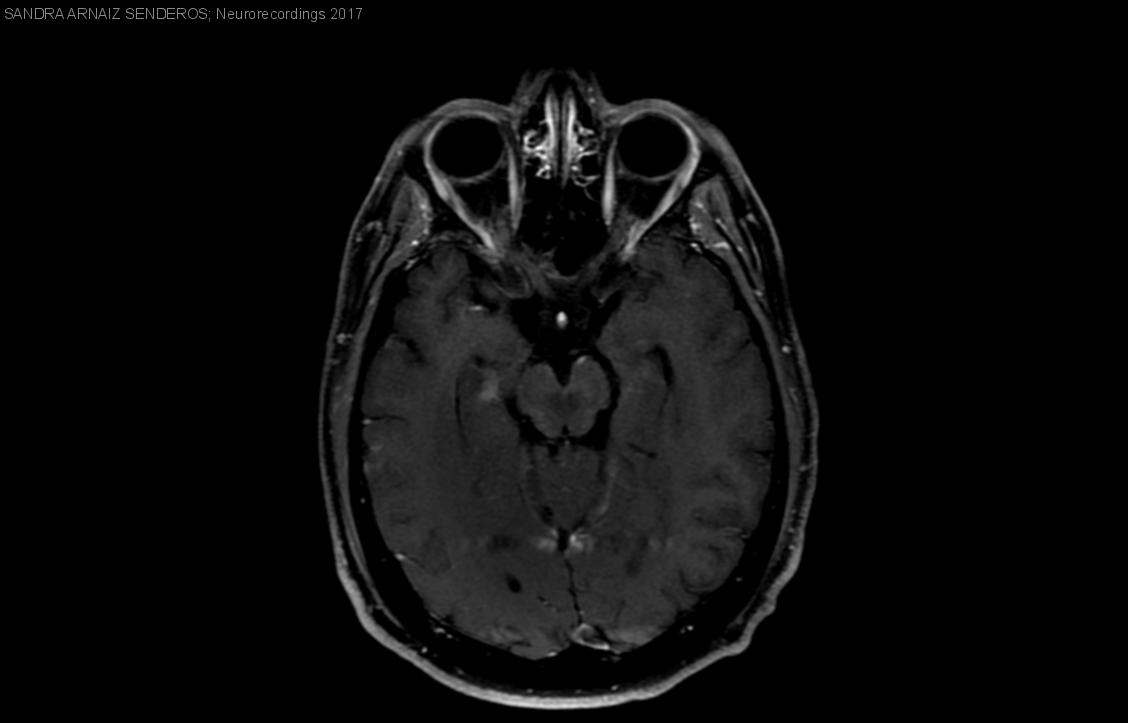

Hombre | 24 años

Diagnóstico final: Neurosarcoidosis

Resumen del caso

Presentamos el caso de un paciente varón de 24 años, sin antecedentes personales ni familiares de interés, que acude a consulta por presentar un cuadro de dos meses de evolución de cefalea holocraneal, visión doble...